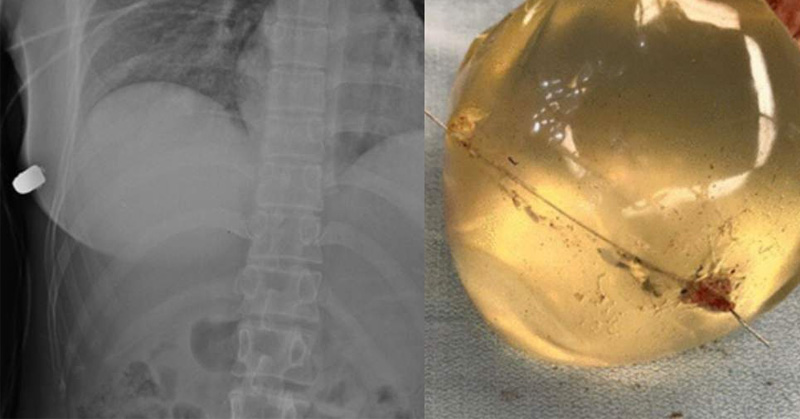

Implante de seno desvía bala y le salva la vida a una mujer

Los médicos creen que una mujer sobrevivió a una herida de bala en el pecho gracias a sus implantes.